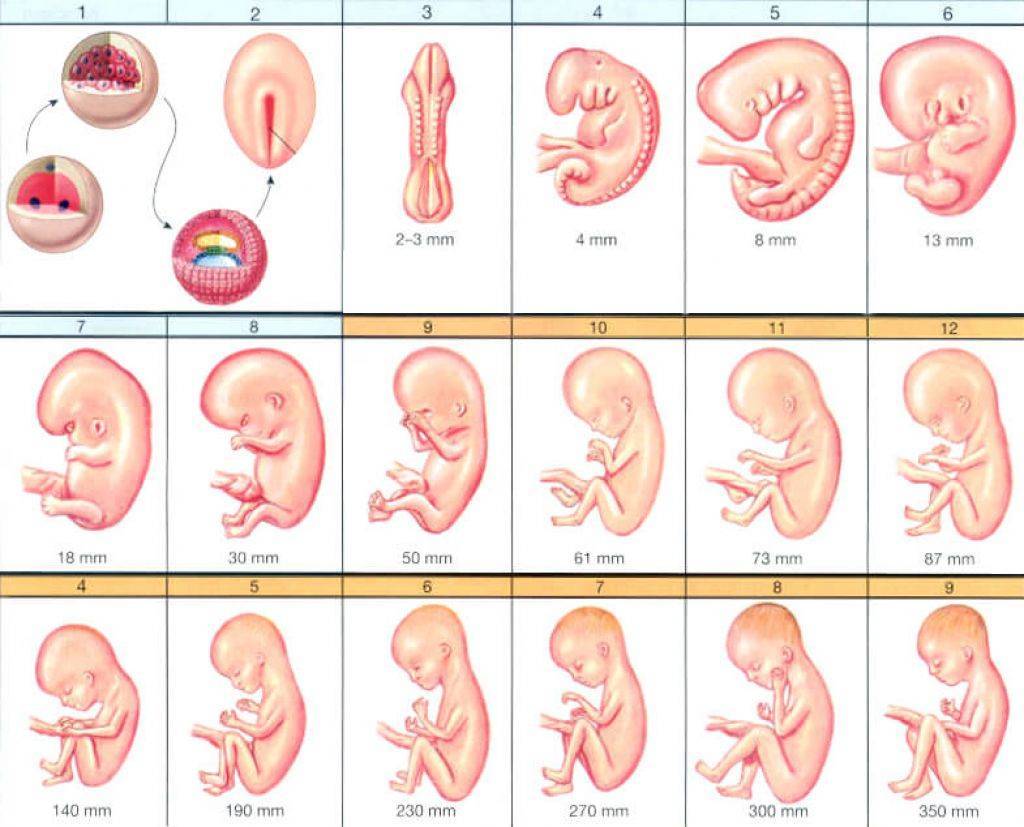

Фотография Плода В Животе

Фотография Плода В Животе 113 фотографий